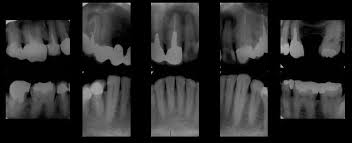

8月24日日曜日9:30-16:30まで熊本市開業の栃原秀紀先生をお迎えして、江坂の松風で基本資料徹底マスターセミナーを行いました。歯科医師、衛生士あわせて35名の参加者がありました。基本資料とは、歯や歯ぐきの状態をレントゲン10枚と口腔内写真(口の中の写真)5枚で記録した資料です。人間の肉眼では、口は1方向の表面しか見ることが出来ません。しかし、基本資料をとる事で 気づかない歯周病や虫歯も発見することができ、最適な治療方法を考えることができます。また定期的に基本資料を撮ることにより、病気の経過観察や回復傾向についても知ることができます。これは、歯をずっと残すために大変重要な手がかりになり、基本資料に変化がなければ歯に自信がもて大きな安心感が得られます。

栃原先生は20年以上、基本資料をとり続け、患者さんの歯の健康に貢献してこられています。セミナーでは基本資料のとり方の実習と参加者の資料の評価をしてもらいました。しっかりした基本資料のある医院は、患者さんの情報の宝庫です。それが歯を長持ちさせる役にたちます。当院でも栃原先生に教えていただいたよう、定期的に基本資料をとって、患者さんのために役立てたいと思っています。